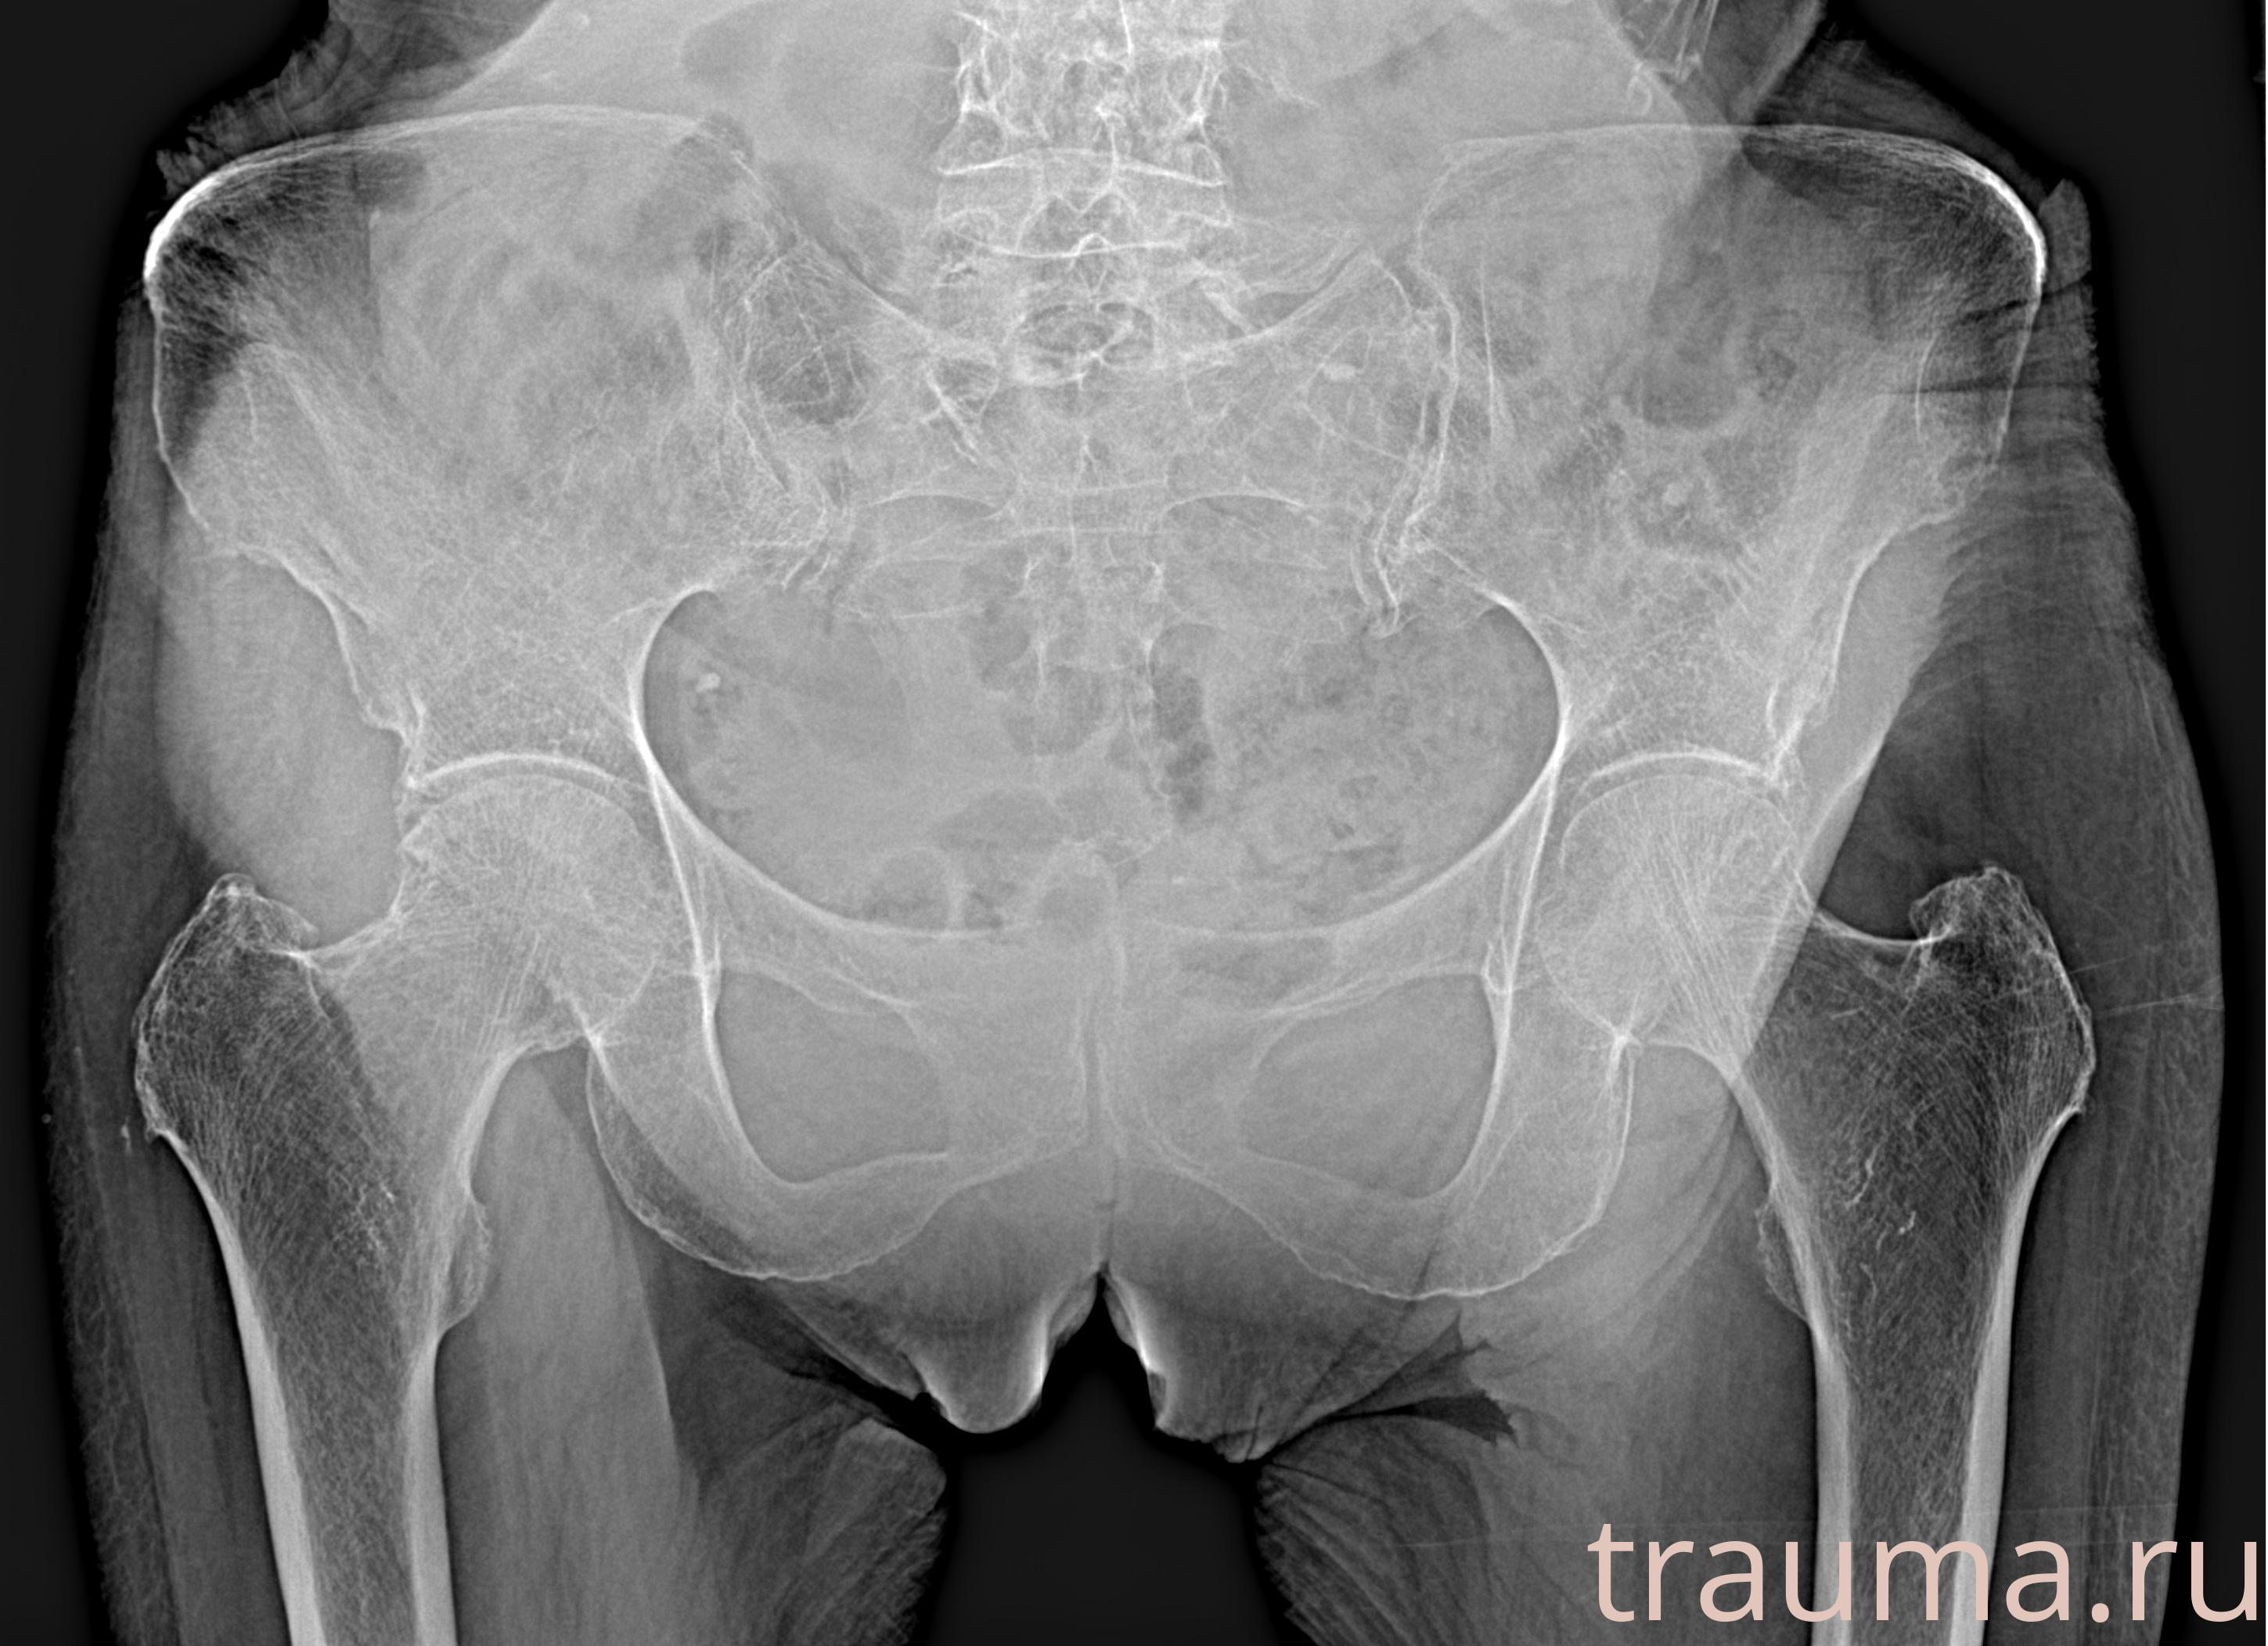

Рентгенограммы

Рентген на дому: по вашему адресу приезжает врач-рентгенолог, травматолог-ортопед с мобильным рентгеновским аппаратом, проводит диагностику травмы или заболевания, делает необходимые рентгенограммы, дает рекомендации по дальнейшему лечению. Получить качественные снимки в домашних условиях возможно благодаря уникальной методике, разработанной МосРентген Центром для института  Склифосовского